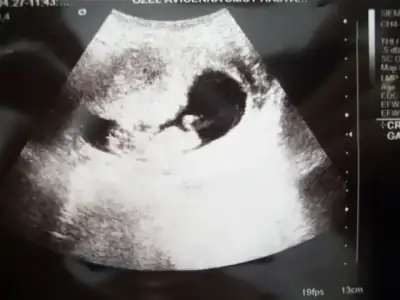

dr soylemeden siz gorun genital nub teorisi ( bebegin cinsiyeti)

Teşekkürler yorum için başka var ama bunlar en net gibi geldiği için koydum bende ultrasonda izlerken yukarı doğru bi çıkıntı gördüm doktor da erkeğe benzetti anladığım kadarıyla sende gayet büyük ve yukarda derken erkeğemi benzettin?

ayynneeenn canim ona biz burda kizdan erkege donen nublar diyoruz ve genelide erkek cikiyooo:66:

14.haftadaydim canim dun fasulyem 8 gun onde gidiyor .cizelgem yanlis yani.erkekler daha cabuk gosteriyor mallar meydandaydi toslaginn:52: benim arkadaslarda hep bu haftalarda ogrendi prensleri hatta bir arkadasla ayni doktora gidiyoruz o 12.haftada ogrendi kiz oldugunu :27:

bak egemcimm goruntu bu doktorumuz boyle bir goruntu yakaladi tam ayaklarini acip alttan cekti :nazar: mallarr meydanda gordugun gibi :) senin belli oldu mu canim sende merak icindesin galibaa